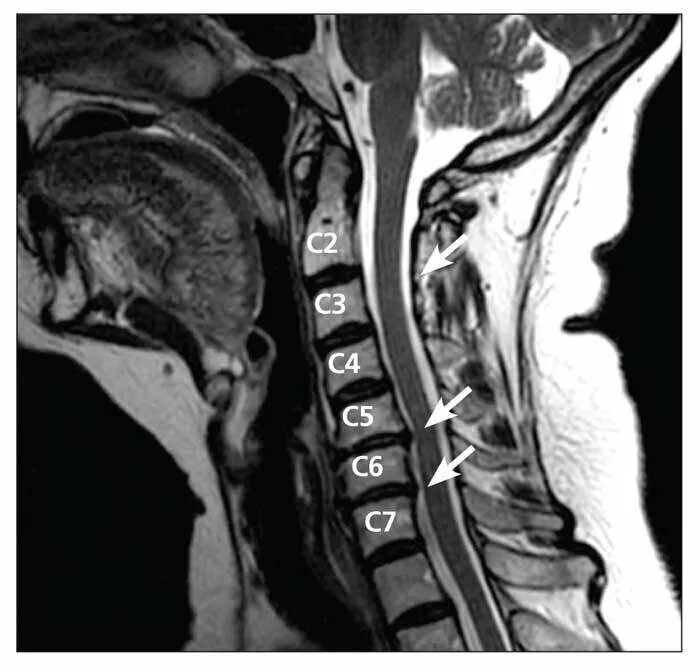

Мрт признаки дегенеративных изменений